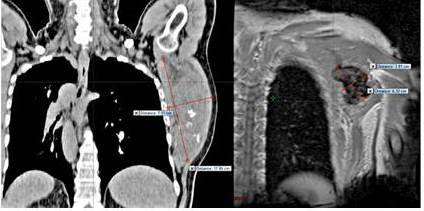

Paciente masculino de 61 años con tumor desmoide en región axilar y escapular izquierda. Imagen de TC en vista coronal antes de la radioterapia (A) y RM vista coronal 1 año después de tratamiento (B).

Paciente masculino de 61 año con tumor desmoide en región escapular y axilar izquierda. Irresecable Recibe RTC3D dosis 6 000cGy con fracciones de 200 cGy. La distribución porcentual de la dosis en los planos axial, coronal y sagital está representada por diferentes tonalidades de colores cuyos valores pueden observarse en la columna de la izquierda.